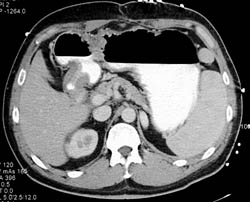

Gastritis